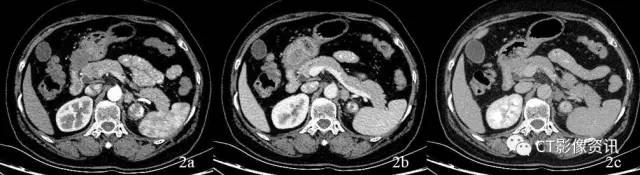

图3:能谱CT扫描,能谱曲线显示肾脏与肾上腺病变不一致,考虑为非同源性病变,肾上腺病变考虑原发病变。

临床价值 能谱成像的重要工具之一能谱曲线是应用能量解析的方法实现组织的单能量成像,然后将得到的单能量CT值再与其对应的能量水平之间的变化关系应用二维坐标系形成能谱曲线。 我们知道,在常规CT诊断过程中,一些不同病变或组织的CT值非常接近,形态也比较类似、难以区分。本病例使用宝石CT的分析工具能谱曲线,根据肾脏病灶和肾上腺区病变的能谱曲线进行比较分析,从而对两者是否同源作出准确判断,解决了仅能依赖形态学变化做出诊断的常规CT很难解决的棘手问题,为影像学及临床疑难病例开拓了新的思路、提供了很有价值的工具。